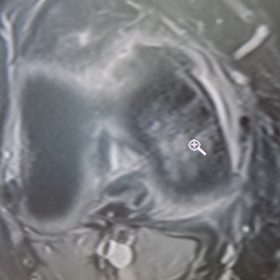

Διάγνωση- Σταδιοποίηση

Διακρίνονται σε 4 στάδια.

Στάδιο Ι. Στένωση του μεσαθριου διαστήματος

Στάδιο ΙΙ. Σκλήρυνση του υποκύμενου χόνδρου

Στάδιο ΙΙΙ. Σκλήρυνση του υπερκείμενου χόνδρου, καταστροφή του υποχόνδρινου οστούν, σχηματισμός οστεόφυτων, οίδημα αρθρώσεως και βραδυνός πόνος

Στάδιο IV. Οστική καθίζηση, καταστροφή μαλακών μορίων μυϊκών ομάδων, υπεξάρθρημα της αρθρώσεως και αλλαγή του μηχανικού άξονα